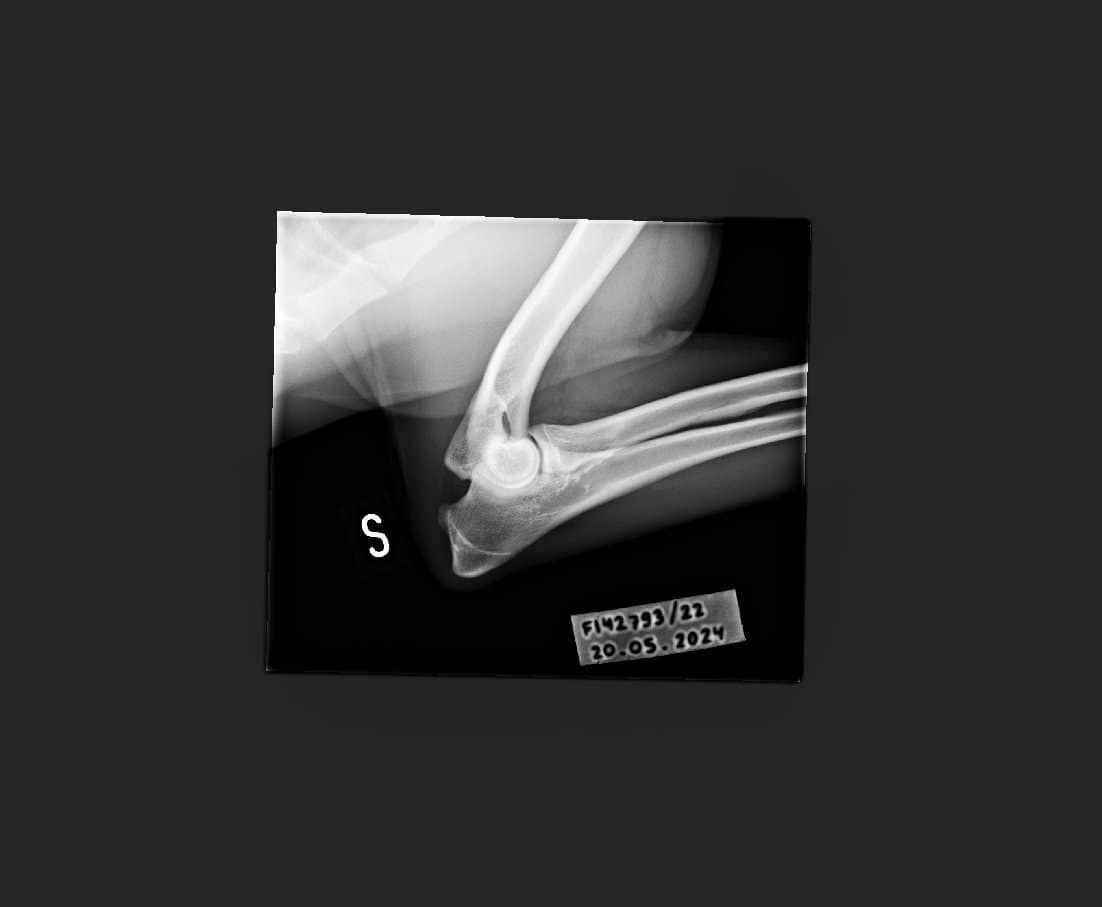

Topin OCD